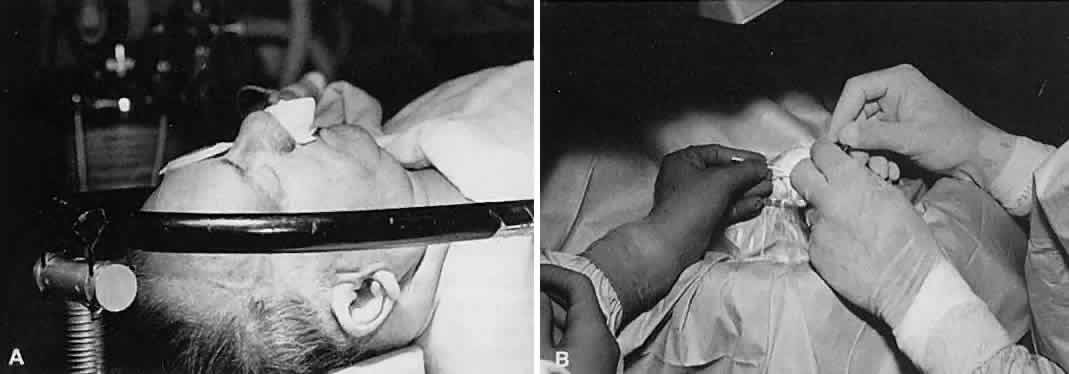

No surgical instruments are intended to be held like a pencil, resting

in the crotch between the thumb and forefinger (Fig. 12).3 In conventional eye surgery, longer instruments usually are rested against

the first metacarpophalangeal joint, with the thumb and first two

fingers encircling the handle. Stability is achieved by resting the side

of the fifth finger on the periorbital facial structures. This method

of holding surgical instruments allows for rotation of the instrument

between the fingertips, by flexing the fingers, or by rotating the

wrist. Great mobility is necessary when using a needle holder (needle

driver) to pass a needle through tissue. When the surgeon encounters

resistance from the tissue, it is usually necessary for the surgeon to

twist the wrist or apply counter pressure on the tissue at the exit site

of the needle. Holding surgical instruments correctly provides the

surgeon with increased flexibility and mobility. The serrations on the

handle, regardless of style, allow the surgeon to hold the instrument

lightly, but firmly. With the level of precision of currently available

instruments, it is never necessary to grasp an instrument tightly. The

tendency to grasp instruments tightly must be avoided because it

decreases flexibility and increases fatigue of the hand and forearm muscles. Any

resistance encountered when placing an instrument into or out

of the eye is secondary to positioning of the instrument. Adjusting

the angle of the instrument or your hands should allow easier placement

of the instrument.  Fig. 12. A. A surgical instrument held like a pencil, resting in the crotch between

the thumb and the forefinger. No surgical instruments are intended to

be held in this manner. B. A longer surgical instrument held resting against the first metacarpophalangeal

joint of the first finger, with the thumb and the first finger

encircling the handle. This position allows for rotation of the instrument

between the fingertips or by flexing the fingers or wrist. C. The surgical instrument is held between the thumb and fingertips of the

second and third digits. This position allows for a more perpendicular

positioning of the instrument on the eye. Fig. 12. A. A surgical instrument held like a pencil, resting in the crotch between

the thumb and the forefinger. No surgical instruments are intended to

be held in this manner. B. A longer surgical instrument held resting against the first metacarpophalangeal

joint of the first finger, with the thumb and the first finger

encircling the handle. This position allows for rotation of the instrument

between the fingertips or by flexing the fingers or wrist. C. The surgical instrument is held between the thumb and fingertips of the

second and third digits. This position allows for a more perpendicular

positioning of the instrument on the eye.